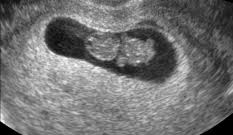

Para la mayoría de los obstetras la semana 8 de embarazo es el momento idóneo para realizar los primeros análisis de sangre y orina y así descartar cualquier complicación relacionada con alguna enfermedad también se han podido llevar a cabo la semana anterior. En la semana 8 de embarazo es prácticamente el comienzo del embarazo. Por otra parte la mujer puede notar que su barriga ha crecido un poco o sentir la ropa ajustada con 8 semanas aunque esto no es evidente en todos los casos.

Pruebas durante la semana 8 de embarazo. Y la madre nota de lleno muchos signos del primer trimestre. No obstante tu cuerpo está cambiando y no tardarás en notar algunos síntomas molestias derivados de tu nuevo estadoGeneralmente en estas fechas se suele pedir cita con el especialista y en ella se puede realizar la primera ecografía para determinar la fecha probable.

Ya deberías haber contactado con tu obstetra. En la semana 8 se empieza a formar la piel del embrión que es translúcida y. Y la madre nota de lleno muchos signos del primer trimestre. Semana 8 de Embarazo Síntomas Cuidados Panza y Ecografía La octava semana de embarazo obstétrica corresponde a la sexta semana embrionaria. Normalmente en la sanidad pública se realizan tres análisis. En la semana 8 de embarazo aún estamos en el segundo mes. Evolución detallada del bebé con su tamaño longi. Pruebas durante la semana 8 de embarazo. Y parece un frijolito saltarín porque no para de moverse y cambiar de posición aunque todavía es pronto para que sientas esta actividad.